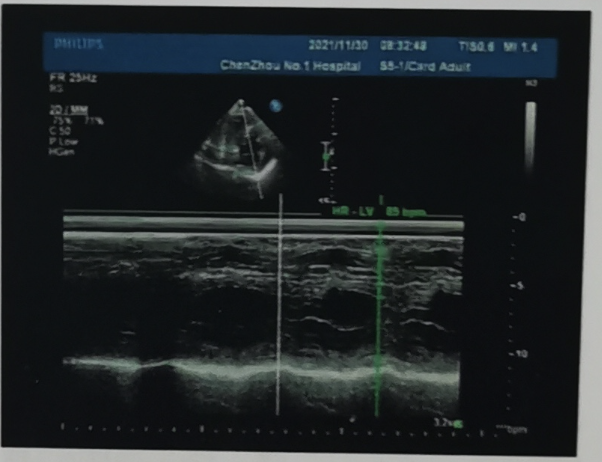

患者超声报告显示:主动脉瓣峰值流速:4.5M/s,左室射血分数EF值:63%,瓣膜及瓣环处见多个强回声团,开放受限,关闭尚可。

诊断:主动脉瓣重度狭窄